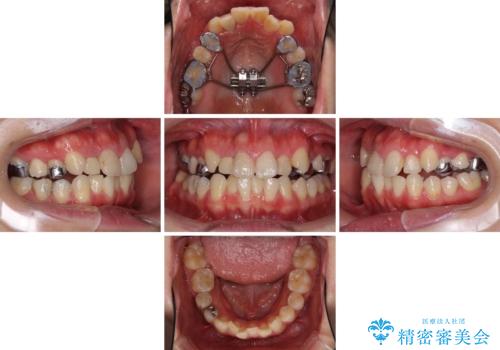

上顎骨の幅が下顎骨よりも小さいので、拡大装置により骨幅を広げて上下関係を改善し、その後インビザラインにて歯並びを整えることとしました。

上下の骨幅を改善したことで、スムーズに歯列矯正を行うことができました。

奥歯の咬み合わせを改善する必要があったため、治療は長期化しましたが、きっちりと仕上げることができました。